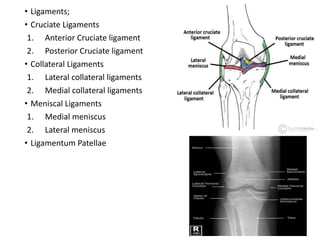

• Ligaments;

• Cruciate Ligaments

1. Anterior Cruciate ligament

2. Posterior Cruciate ligament

• Collateral Ligaments

1. Lateral collateral ligaments

2. Medial collateral ligaments

• Meniscal Ligaments

1. Medial meniscus

2. Lateral meniscus

• Ligamentum Patellae